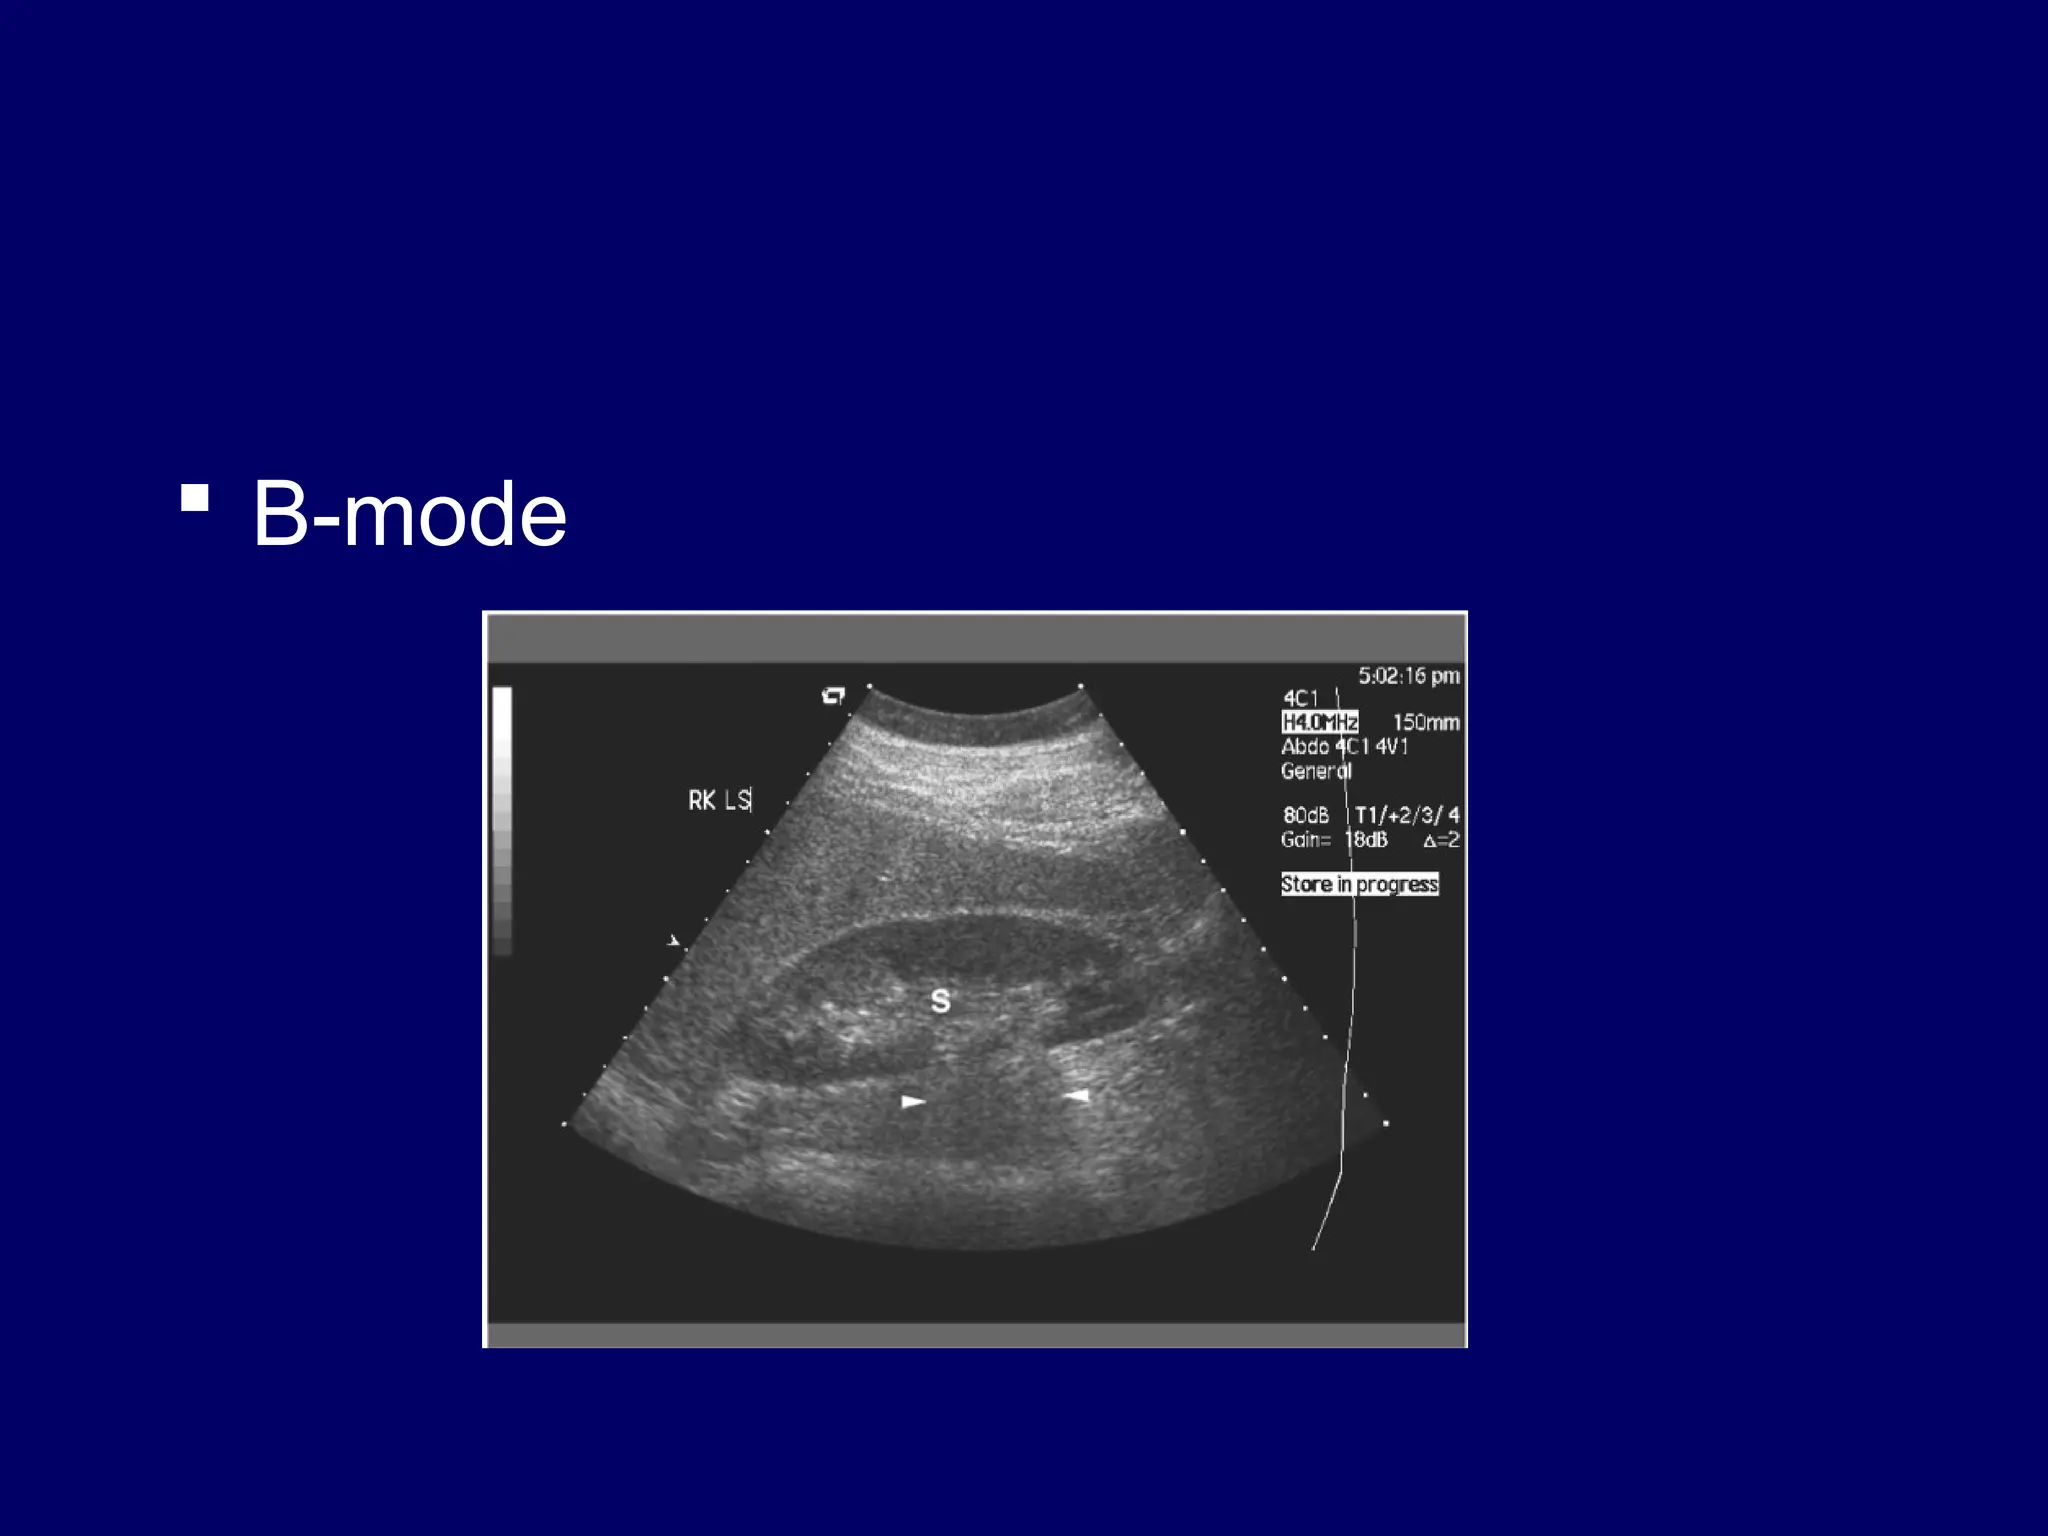

 Imaging methods

– B- mode (grey scale display)

 B-mode